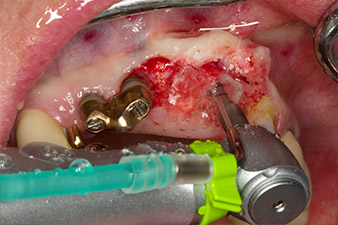

Nach primärer Abheilung werden die Weichgewebe mithilfe der basal unterfütterten Brücke ausgeformt. Zwei Monate später erfolgt die Freilegung mit einem leicht palatinal gelegten Kieferkammschnitt (Abb. 2).

Der Alveolarknochen erweist sich an Position 22 als ausreichend dimensioniert. Die Abbildungen 2 und 4 zeigen die Implantatbett-Aufbereitung, den Gewindeschnitt und die Implantation mit dem Implantmed.

Der neue Implantologiemotor wird jeweils mit den geeigneten chirurgischen Winkelstücken von W&H verwendet.